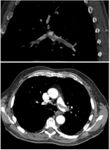

On CT scan, pulmonary emboli can be classified according to level along the arterial tree.

Segmental and subsegmental pulmonary emboli on both sides

CT pulmonary angiography showing a "saddle embolus" at the bifurcation of the main pulmonary artery and thrombus burden in the lobar arteries on both sides.